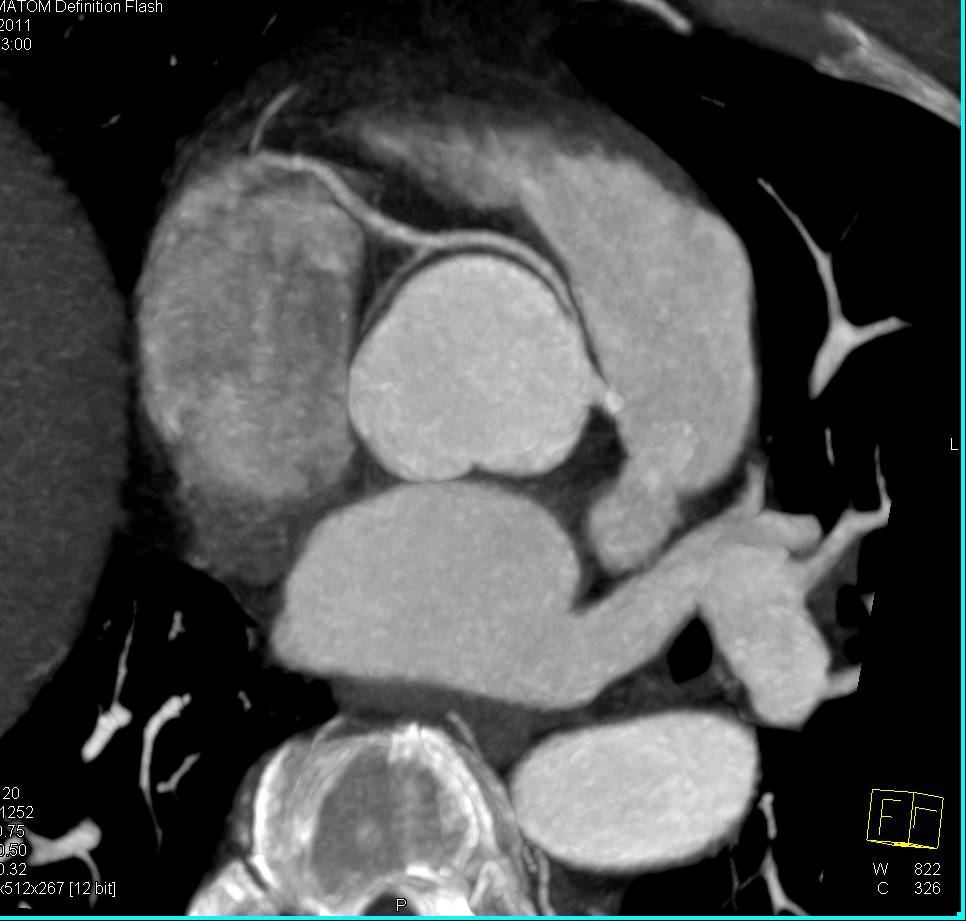

Focal Pseudoaneurysms off the Root